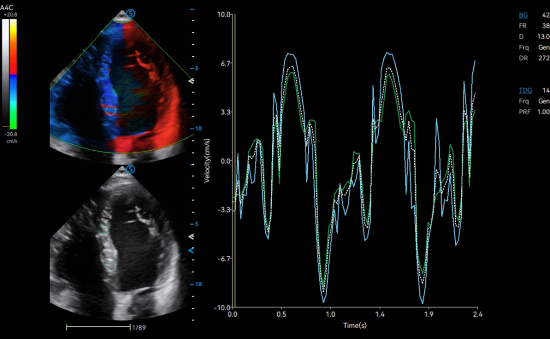

TDI QA quantitatively analyzes the myocardial motion with multiple sampling points for convenient comparison and evaluation.